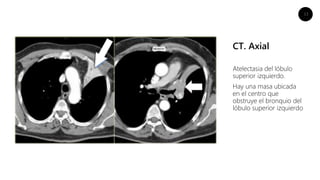

CT. Axial

Atelectasia del lóbulo

superior izquierdo.

Hay una masa ubicada

en el centro que

obstruye el bronquio del

lóbulo superior izquierdo